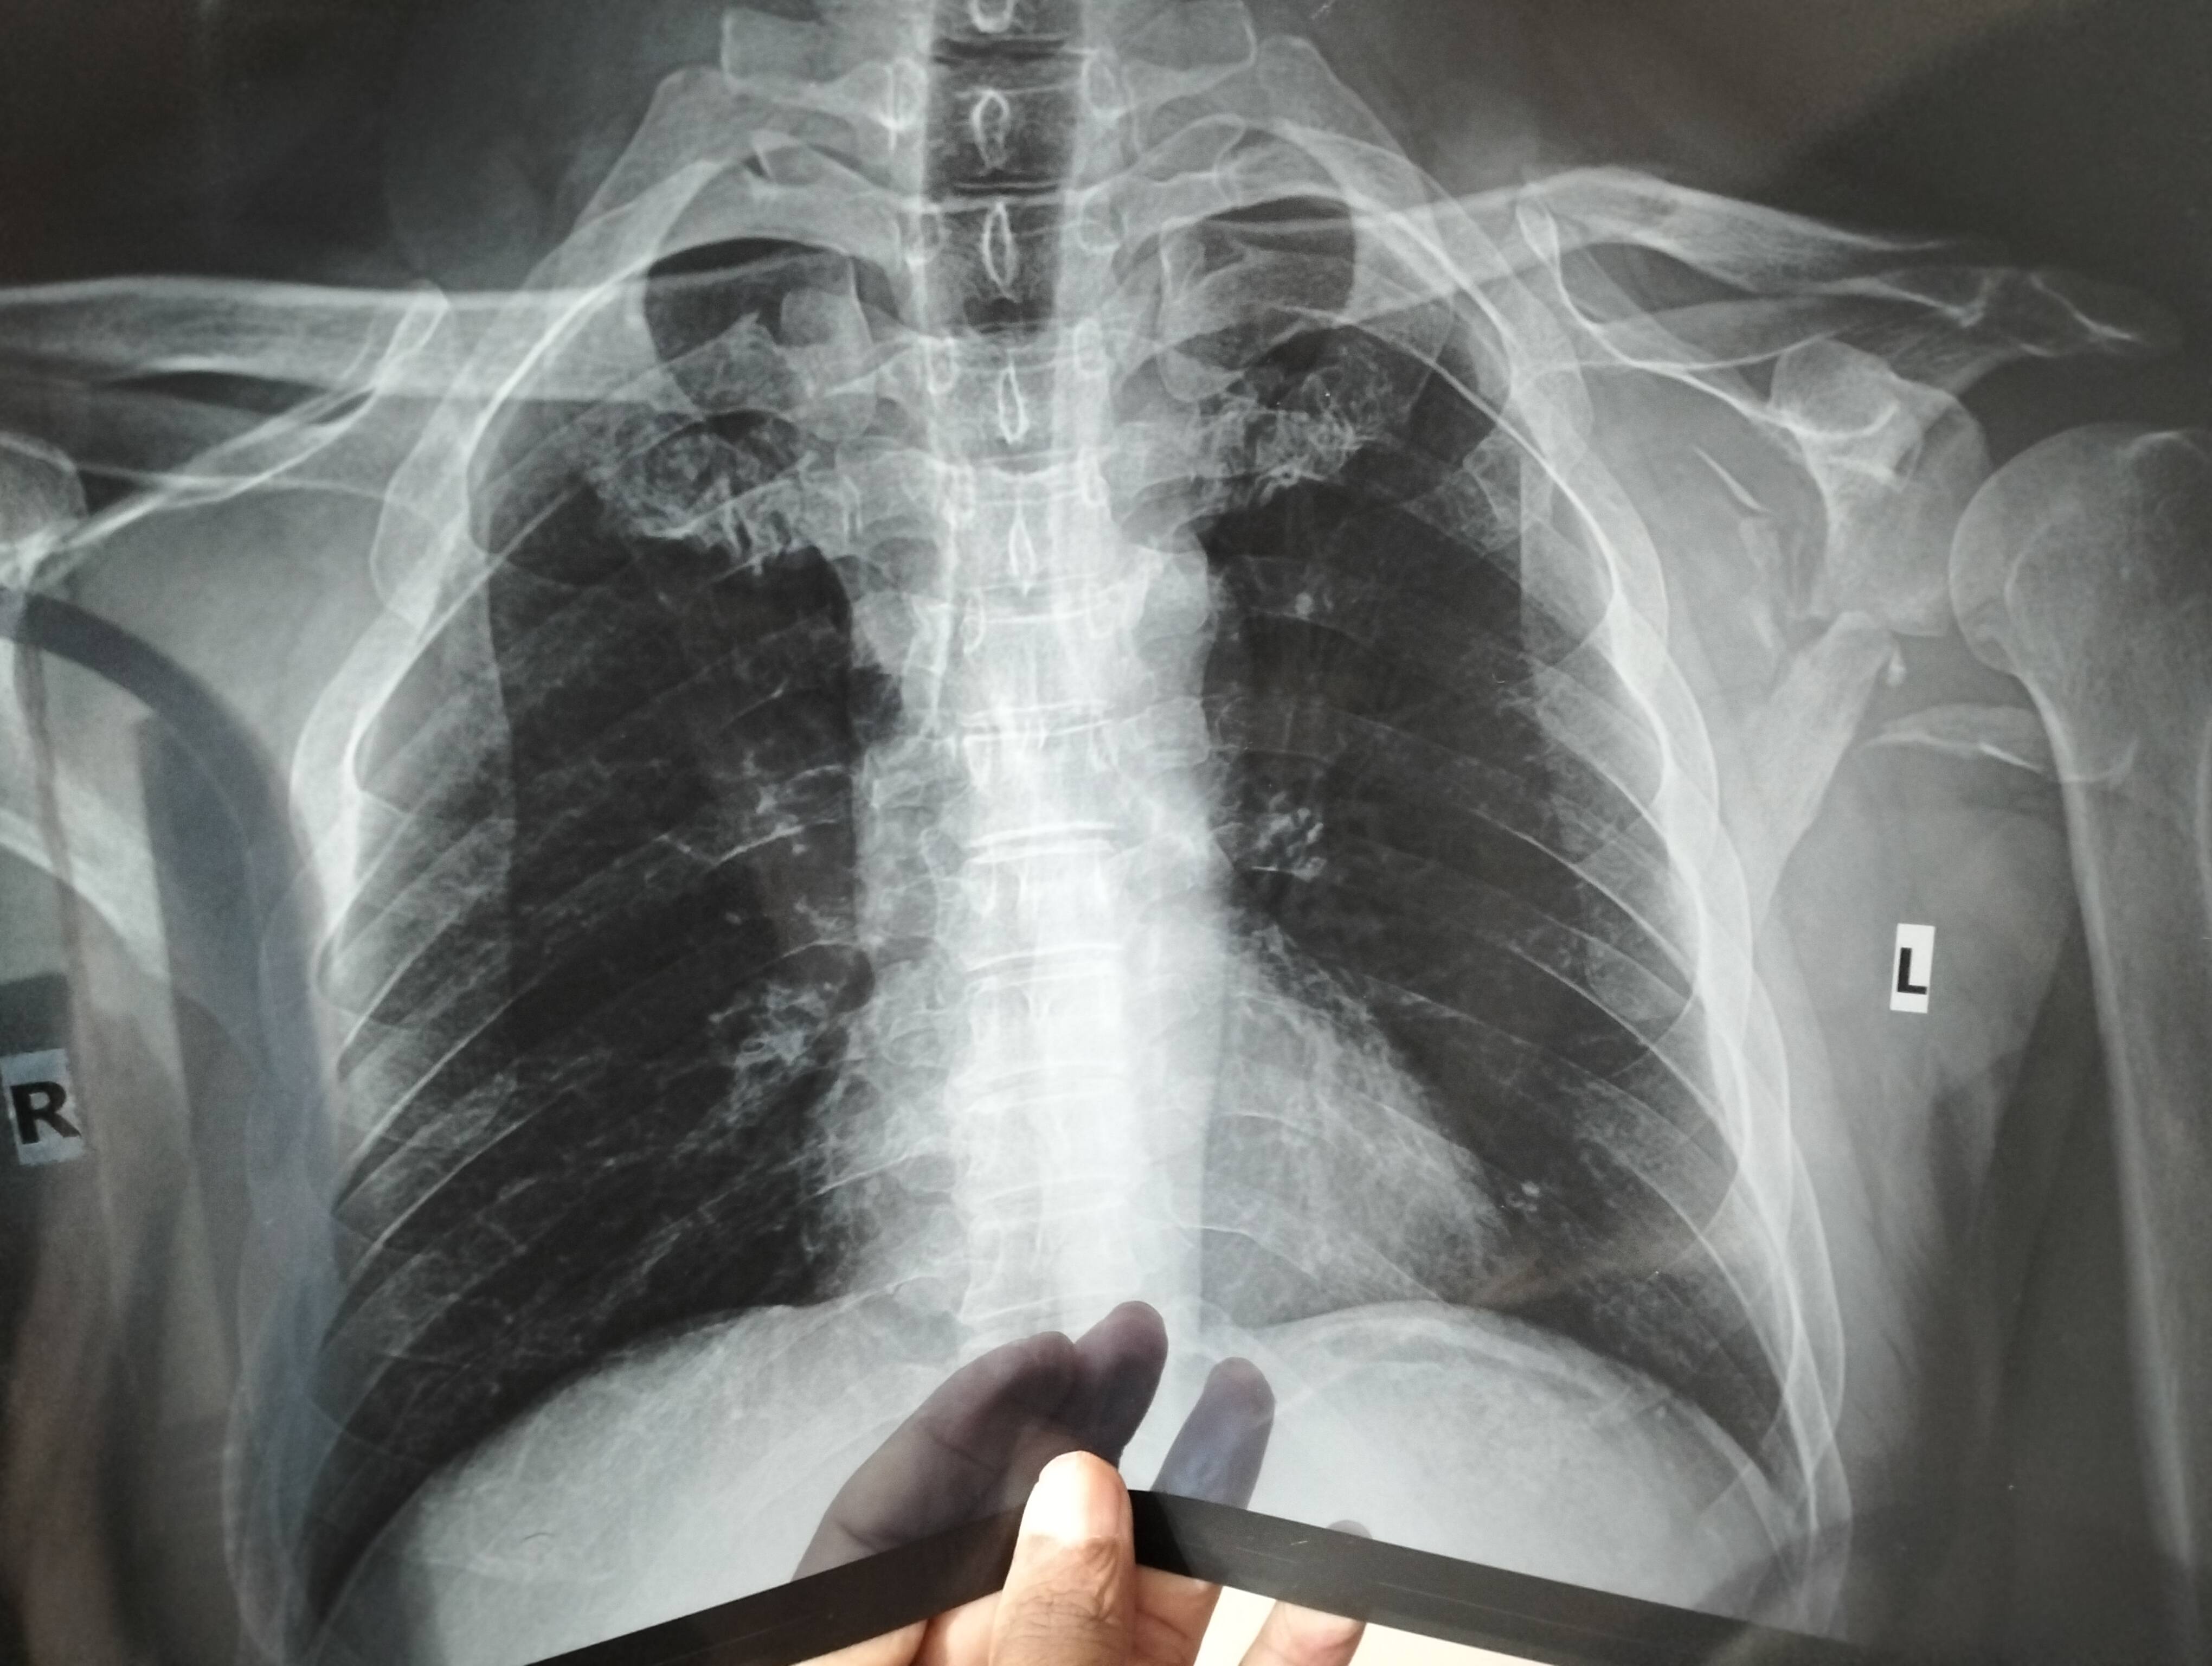

On 22th October, 2022 my clavicle and scabula got fractured due to a bike accident. Is it okay if it gets joined automatically? Or is there any better way to treat it so that no problem occurs in future?

Some doctors suggested that an operation can be conducted to straighten the clavicle, some said operation isn't needed. What's your suggestion?

By the way, I've sent messages and x-ray images in your WhatsApp. Your suggestion would be much appreciated.